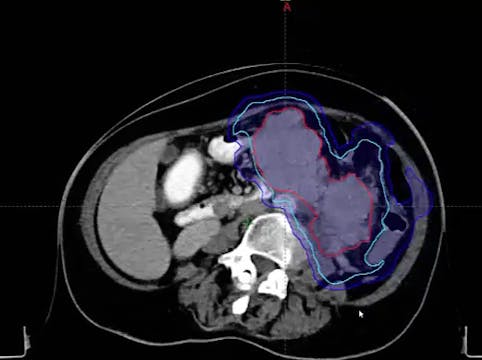

Invasive ductal carcinoma, locally advance breast cancer, metastatic cancer, CT simulation procedure, CT techniques, contouring, breast cancer treatment fields